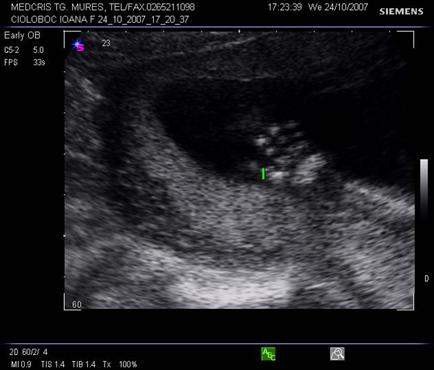

Aspecte normale ecografice in trimestrul II si III de sarcina